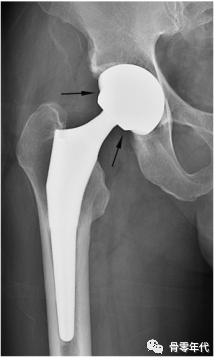

半关节置换术(a)和全髋关节置换术(b)的简单x线片。双极半关节置换术(a)中,髋臼软骨下骨板和相邻关节间隙(箭头)得以保留,髋臼杯外表面光滑而非粗糙(箭头)。杯子的弦线(红线)偏离球体的直径。在THA (b)中,软骨下骨终板和软骨间隙缺失(箭头),杯和骨之间的界面光滑,显示出外部球形轮廓的细微压痕(箭头)。杯子的弦线(红线)接近球体的直径(黑线)。在这两幅图像中,黑线表示球体的直径,而红线表示连接髋臼杯或双极头的内外边缘的弦线。